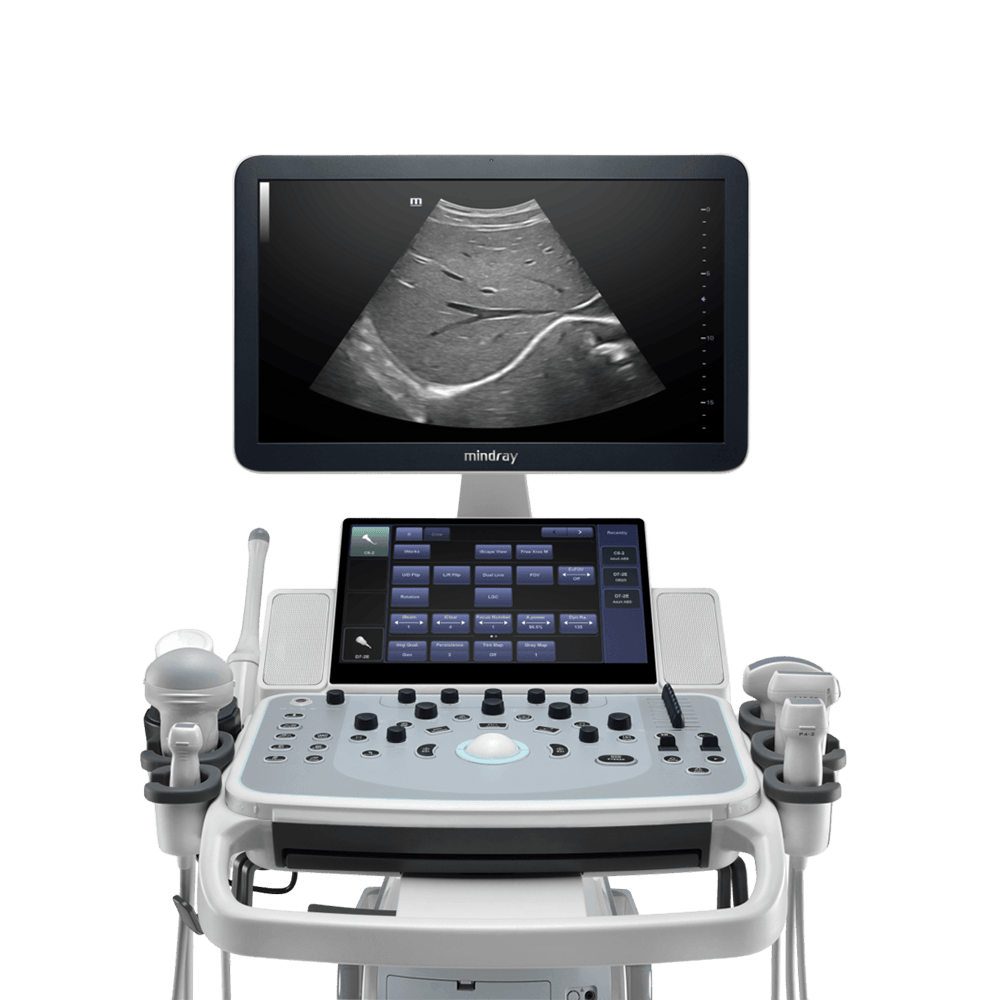

Ecógrafo Mindray DC-40

- Mindray cree y tiene fe en que en condiciones difíciles de trabajo, un sistema de ultrasonido debe tener una imagen nítida, ser fácil de usar y garantizar la confiabilidad, para ello ha aplicado en su modelo de ecógrafo DC-40 variadas características que permite imágenes de alto rendimiento como FullHD.